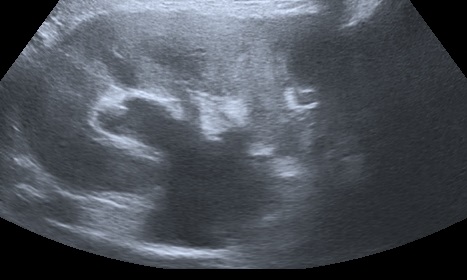

The following images represent an abnormal passageway between the ureter and the vaginal apex following a complicated hysterectomy.